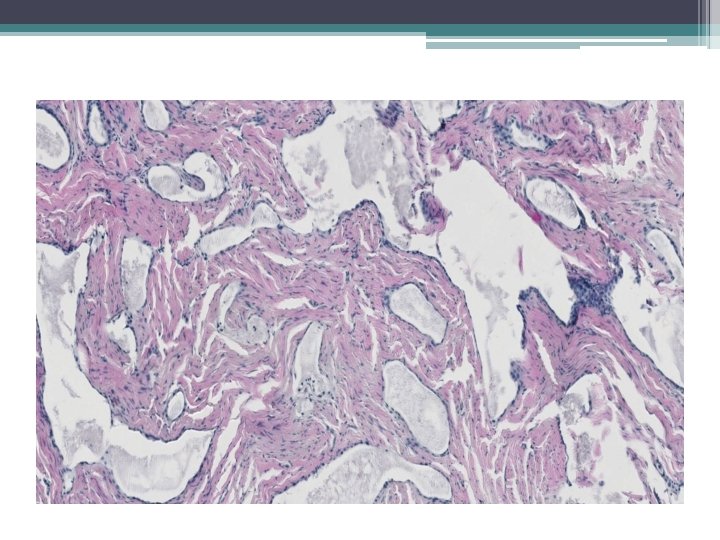

Mikro:

Ektopická prostatická tkáň • • vzácně lokalizace: cervix, vagína věk 21 -65 let mikroskopicky : tubuly a aciny některé papilární, některé kribriformní, s dlaždicovou metaplázií

• Mikroskopicky: • dobře ohraničená hnízda s vrstevnatým dlaždicovým epitelem a tubuly vystlané jednou až dvěma řady kubických buněk, nebo dlaždicovými buňkami. V centru hnízd může byť přítomná nekróza s kalcifikací, nebo keratinové perly.